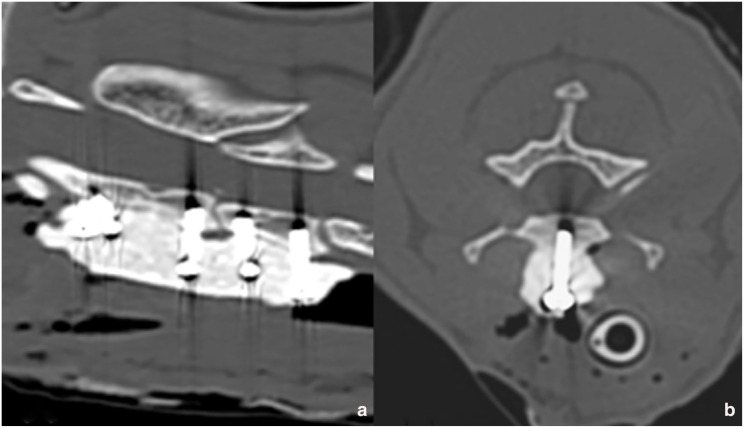

病例摘要:一只两岁大的绝育雌性短毛猫在一次交通事故后出现四肢瘫痪。脊柱放射线检查显示,C2-C3 颈椎脱位,CT 扫描证实了这一点。通过腹侧入路使用螺钉和聚甲基丙烯酸甲酯(PMMA)进行了手术稳定。术后 CT 扫描显示,植入物的位置正确,半脱位得到了很好的缓解。术后,猫咪的神经功能迅速恢复正常:外伤引起的颈椎半脱位在猫科动物中并不常见,但应在鉴别诊断中予以考虑。本报告描述了使用螺钉和 PMMA 对猫的 C2-C3 颈椎脱位进行手术治疗的情况。这是首例通过手术治疗猫颈椎轴下脱位的病例报告。

Case summary: A 2-year-old spayed female domestic shorthair cat presented with tetraparesis after being involved in a road traffic accident. Survey spine radiographs revealed a C2-C3 cervical subluxation, which was confirmed by a CT scan. Surgical stabilisation was performed using screws and polymethyl methacrylate (PMMA) via a ventral approach. A postoperative CT scan demonstrated correct implant positioning and good reduction of the subluxation. After surgery, the cat rapidly recovered to a neurologically normal status.